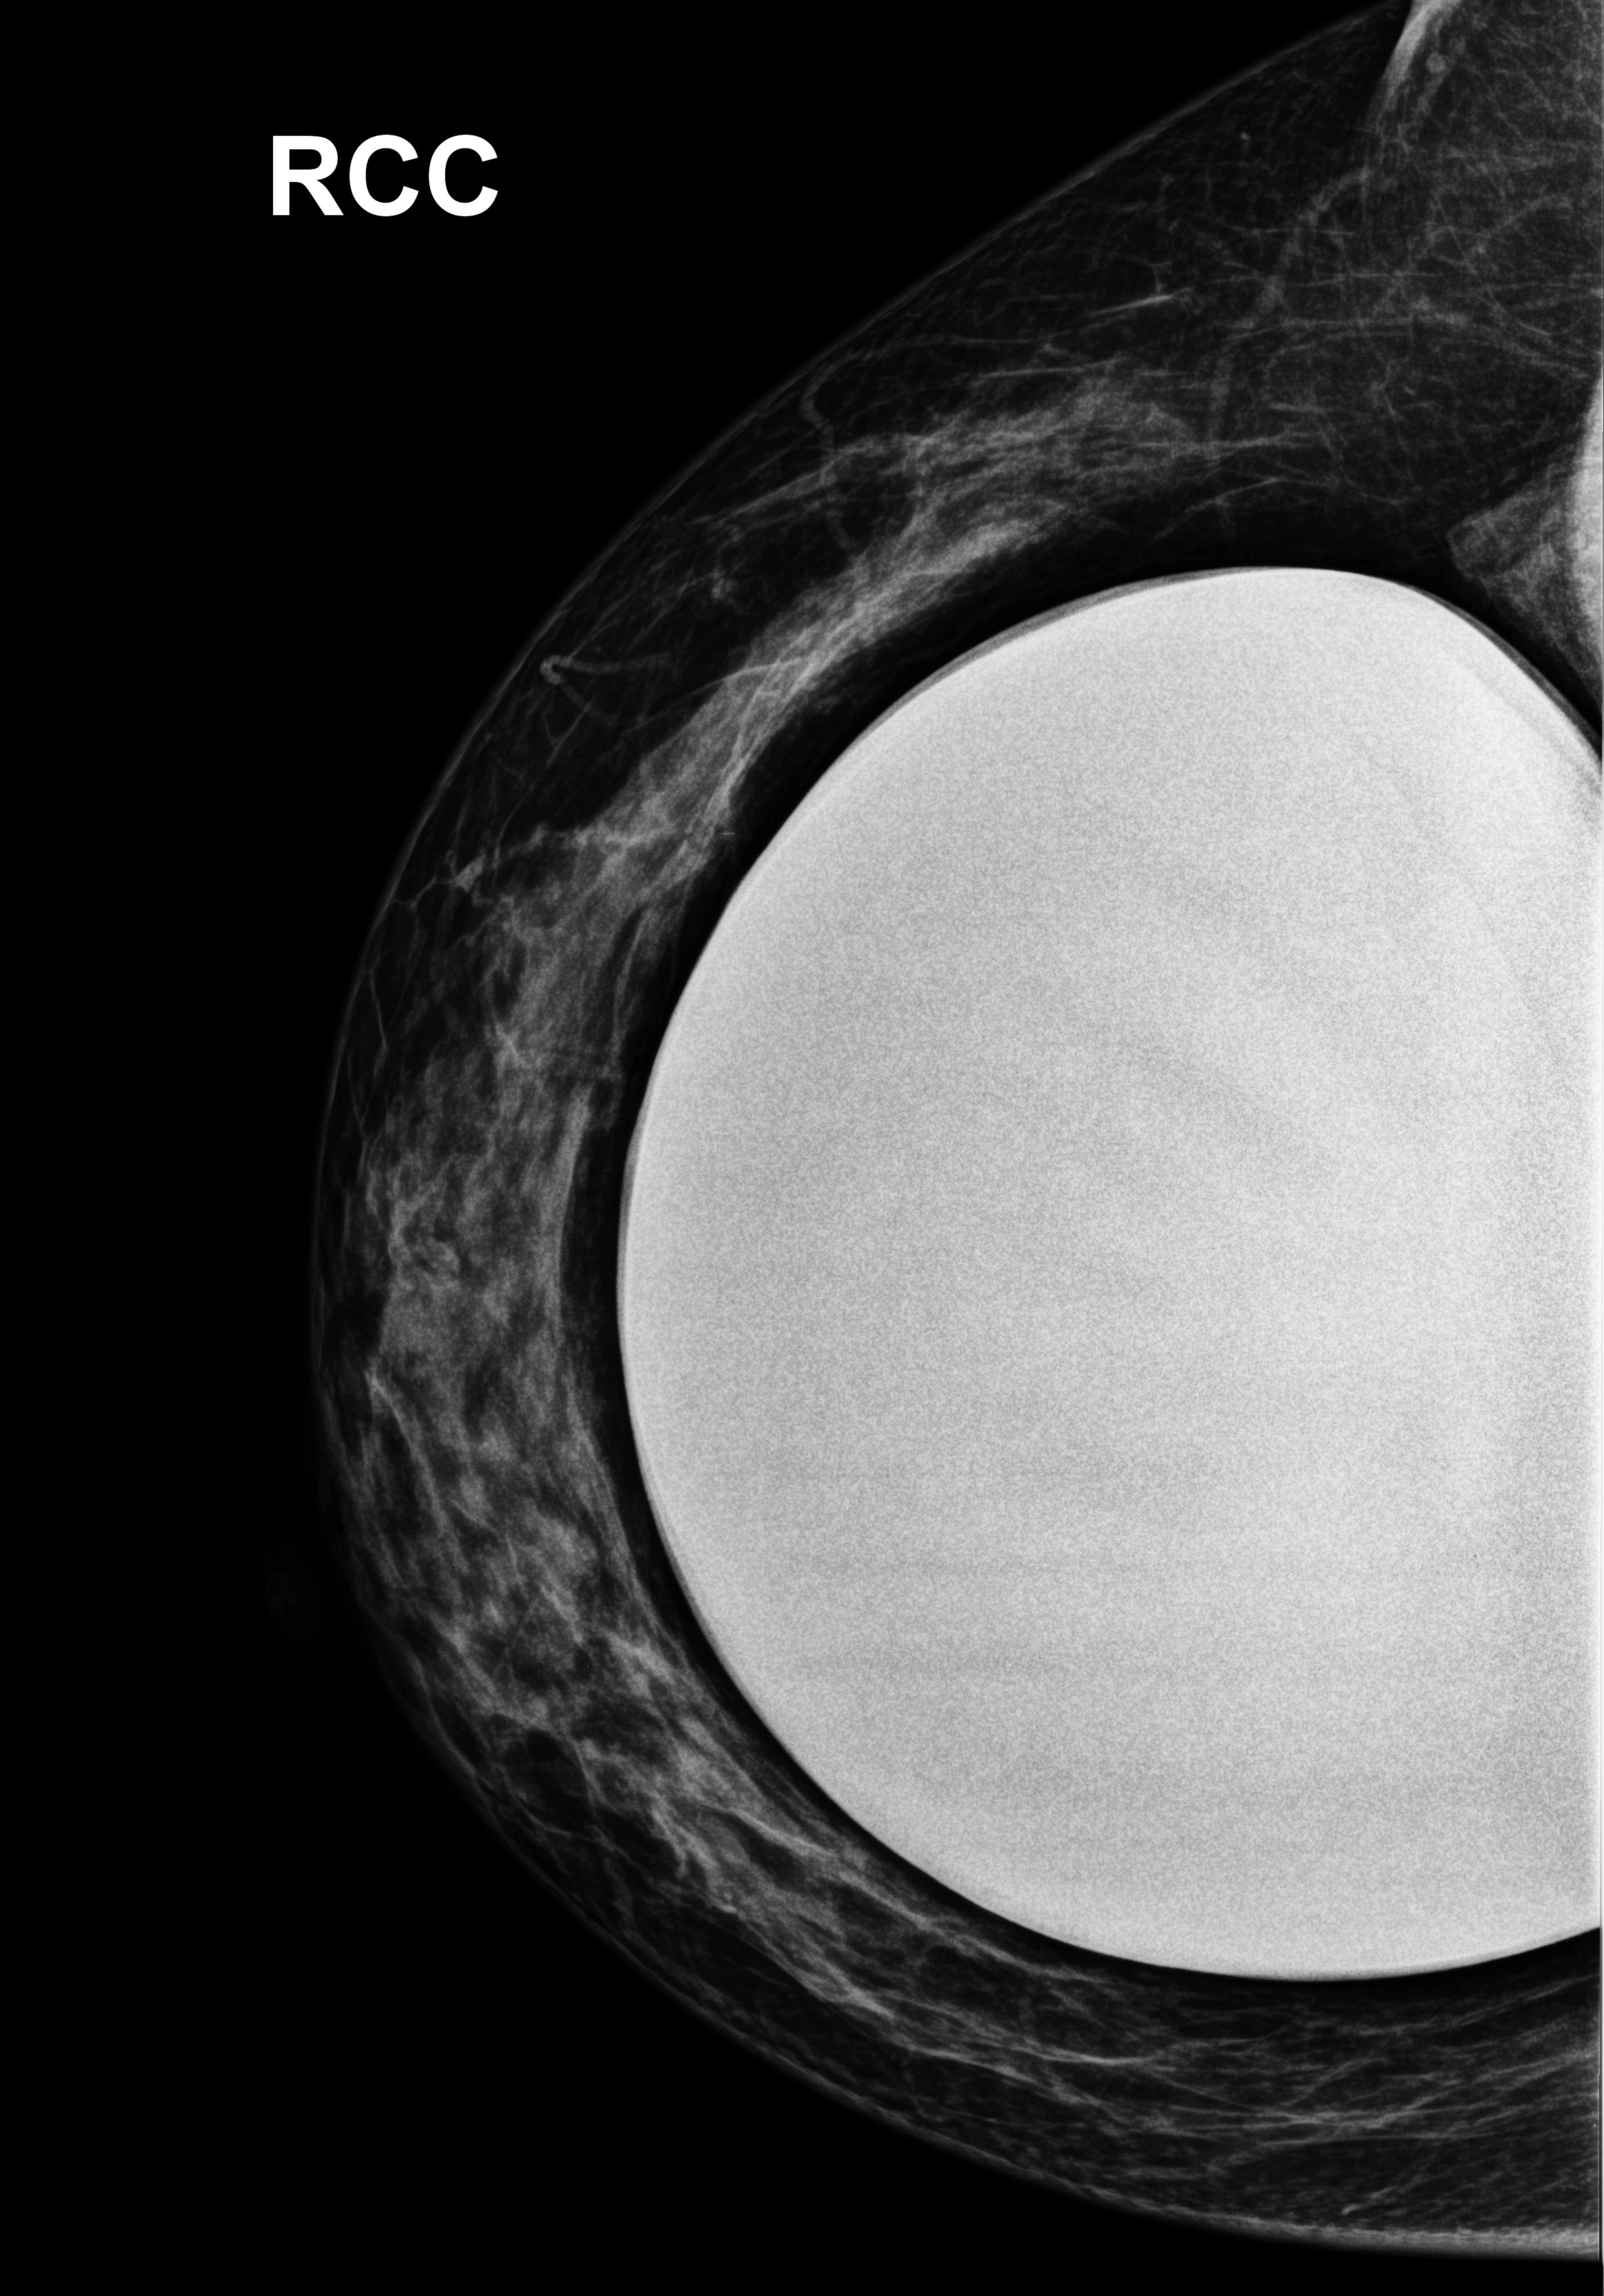

• Tuyến vú

• Tổn thương nguy cơ cao

Tổn thương nguy cơ cao

Tăng sản ống không điển hình (Atypical ductal hyperplasia)